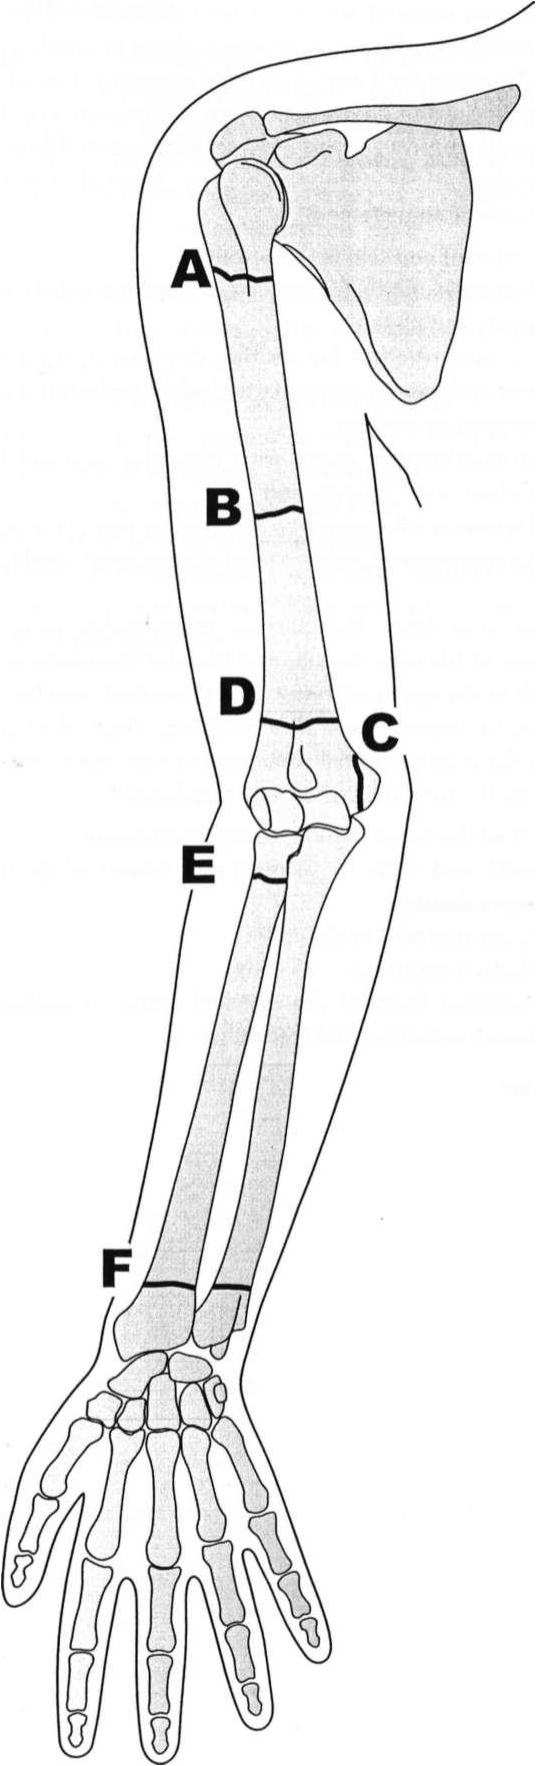

Directions: Match each of the following questions with

the most likely fracture pattern (letterhead) depicted in, using each answer once, more than once, or not at all.

Q.A : Most likely to cause weakness of the extensor muscles of the wrist and hand; extension of forearm typically not affected; sensation of dorsal hand affected

Q.B : May result in teres minor weakness

Q.C : Weakness of flexion and adduction of wrist, paralysis of hypothenar muscles and most deep muscles of the hand, some weakness in thenar muscles

Q.D : Shoulder abduction weakness

Q.E : High likelihood of ulnar nerve injury only

Q.F : Median nerve damage, paralysis of hypothenar muscles, some thenar muscles, and most of the deep muscles of the hand; flexion and adduction of wrist spared

Q.G : Can be associated with brachial plexus injuries

Q.H : Most likely to cause combined radial, medial, and ulnar nerve injuries

A.-B

B.-A

C.-C

D.-A

E.-C

F.-F

G.-A

H.-D

Fracture of them proximal humerus (A) can result in injury to the axillary

nerve (G5-6), which innervates the teres minor and deltoid muscles. This can result in sensory loss at the shoulder as well as shoulder abduction weakness. There is also a chance of concomitant brachial plexus injury with such a fracture due to the proximity of the proximal humerus to the brachial plexus. The radial nerve runs down the posterior aspect of the arm and is at risk for injury during fractures of the midhumeral shaft as it winds around the spiral groove (B). This could cause paralysis of the wrist and hand extensor muscles. Since the fibers that innervate the triceps muscle often arise proximal to the spiral groove, extension of the forearm may not be affected by midhumeral fractures, and some supination is possible due to an intact biceps brachii muscle. Fracture in the vicinity of the medial epicondyle may result in ulnar nerve damage only (C), which can produce weakness of flexion and adduction of wrist, paralysis of hypothenar muscles and most deep muscles of the hand, as well as some weakness in select thenar muscles. Injury of the ulnar nerve by fracture of the distal ulna can result inweakness or paralysis of hypothenar, some thenar, and intrinsic hand muscles but often spares innervation of the wrist (flexion, adduction), since these nerves often arise more proximally. If there is also a concomitant distal radial fracture, injury to the median nerve may accompany the ulnar nerve injury (F) and produce loss of sensation of the lateral side of the palm without sensory loss on the palmar sides of the first, second, and third digits (superficial branch of the median nerve) as well as marked weakness of thumbflexion and abduction, inability to oppose the thumb, inability to fully extend the second and third digits, and sensory loss along the palmar side of the first, second, and third digits (deep branch in carpal tunnel). A fracture of the distal humerus (D) is most likely to result in combined radial,median, and ulnar nerve injuries